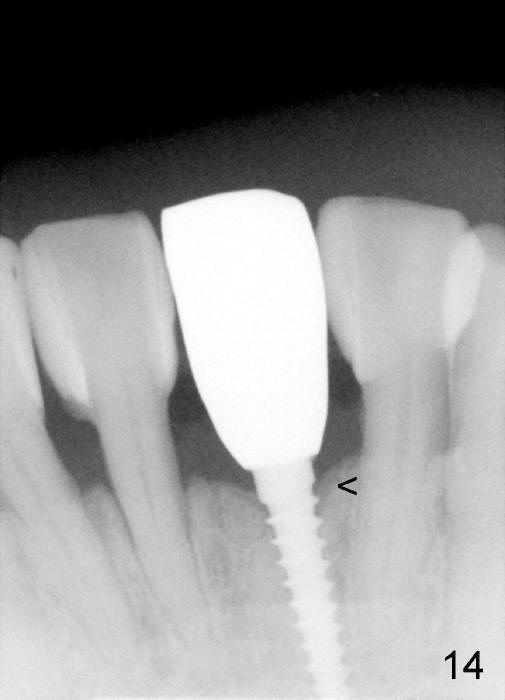

Fig.10,11 show 7 day follow up.  The permanent crown is seated 4.5 months postop (Fig.12).  Minimal bone resorption occurs at the crest 4 months postop (Fig.13), which is most likely associated with conservative approach (flapless).  The patient returns for follow up 2.5 months post cementation (Fig.14,15).  The implant remains in the bone 4 years post cementation (Fig.16 CT coronal section; lingual thread exposure, corresponding to preop defect in Fig.1).   There is mild coronal bone resorption 5 years 4 months post cementation (Fig.17).